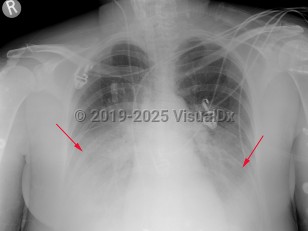

Pericardial effusionPericardial effusion

Cardiac tamponadeCardiac tamponade

PericarditisPericarditis